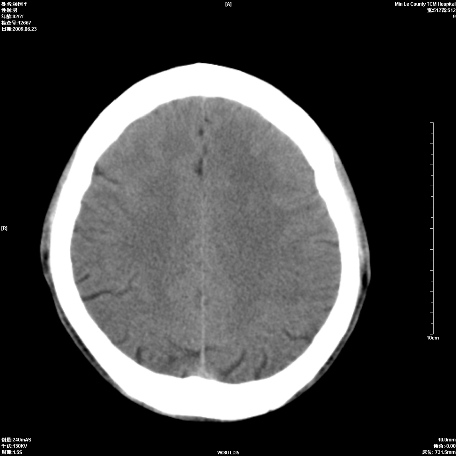

以下是引用随光逐影在2009-6-23 14:30:00的发言:[br]1)颅脑ct轴位平扫颅内未见明确异常。2)左侧额部头皮软组织肿胀。[br][br](双侧苍白球见对称性钙斑,透明隔间腔与vergae腔并存)